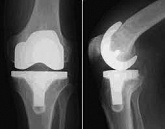

Еndoprosthesis of knee joint

In the late stages of arthrosis of the knee joint, accompanied by a pronounced restriction of the volume of movements, constant intense pain, deformity of the limb, the only way to recover is to replace the affected joint with an artificial joint - arthroplasty.

This method allows you to return the correct form of the limb, the full volume of movements in the joint, relieve the constant pain and crunch during movements and, as a result, significantly improve the patient's quality of life.

Below are presented X-ray photographs and photographs, illustrating the amount of motion in the affected joint before and after surgery.